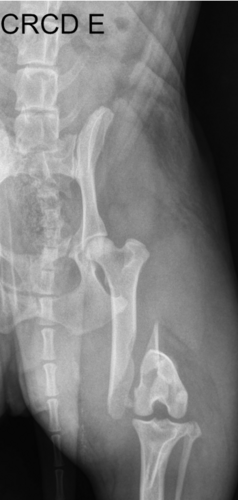

O Lupi é um membro muito querido da nossa família e, infelizmente, ele sofreu um acidente grave e quebrou o fêmur.

Levamos o Lupi a uma clínica especializada em Porto Alegre, e após exames e um Raio-X, o diagnóstico foi confirmado. Ele sente muita dor e o único alívio que tem tido é com doses fortes de Tramadol, um analgésico potente. É doloroso vê-lo dopado e sofrendo, sem a alegria de antes.

A única solução definitiva para que o Lupi pare de sofrer e volte a ter qualidade de vida é uma cirurgia ortopédica de emergência.